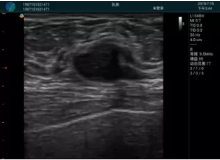

清晰顯示腺體內(nèi)低回聲快影,邊界清晰,包膜較光滑

確定進針路徑并實時監(jiān)測抽吸針與腫塊位置關系